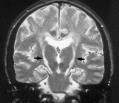

ALS診断のための検査:MRI

ALSでは通常MRIでは異常所見は見られないが、他疾患の鑑別が主な役割。

時にFLARIRやT2強調画像で、皮質脊髄路にそって高信号が認められることがある。

内包後脚および大脳脚に淡いT2高信号が認められる。

大脳脚レベル以下や中心前回皮質下まで続く高信号はALSの病的変化と考えられる。

T2強調像や磁化率強調像で中心前回皮質の信号がみられる頻度が高い。